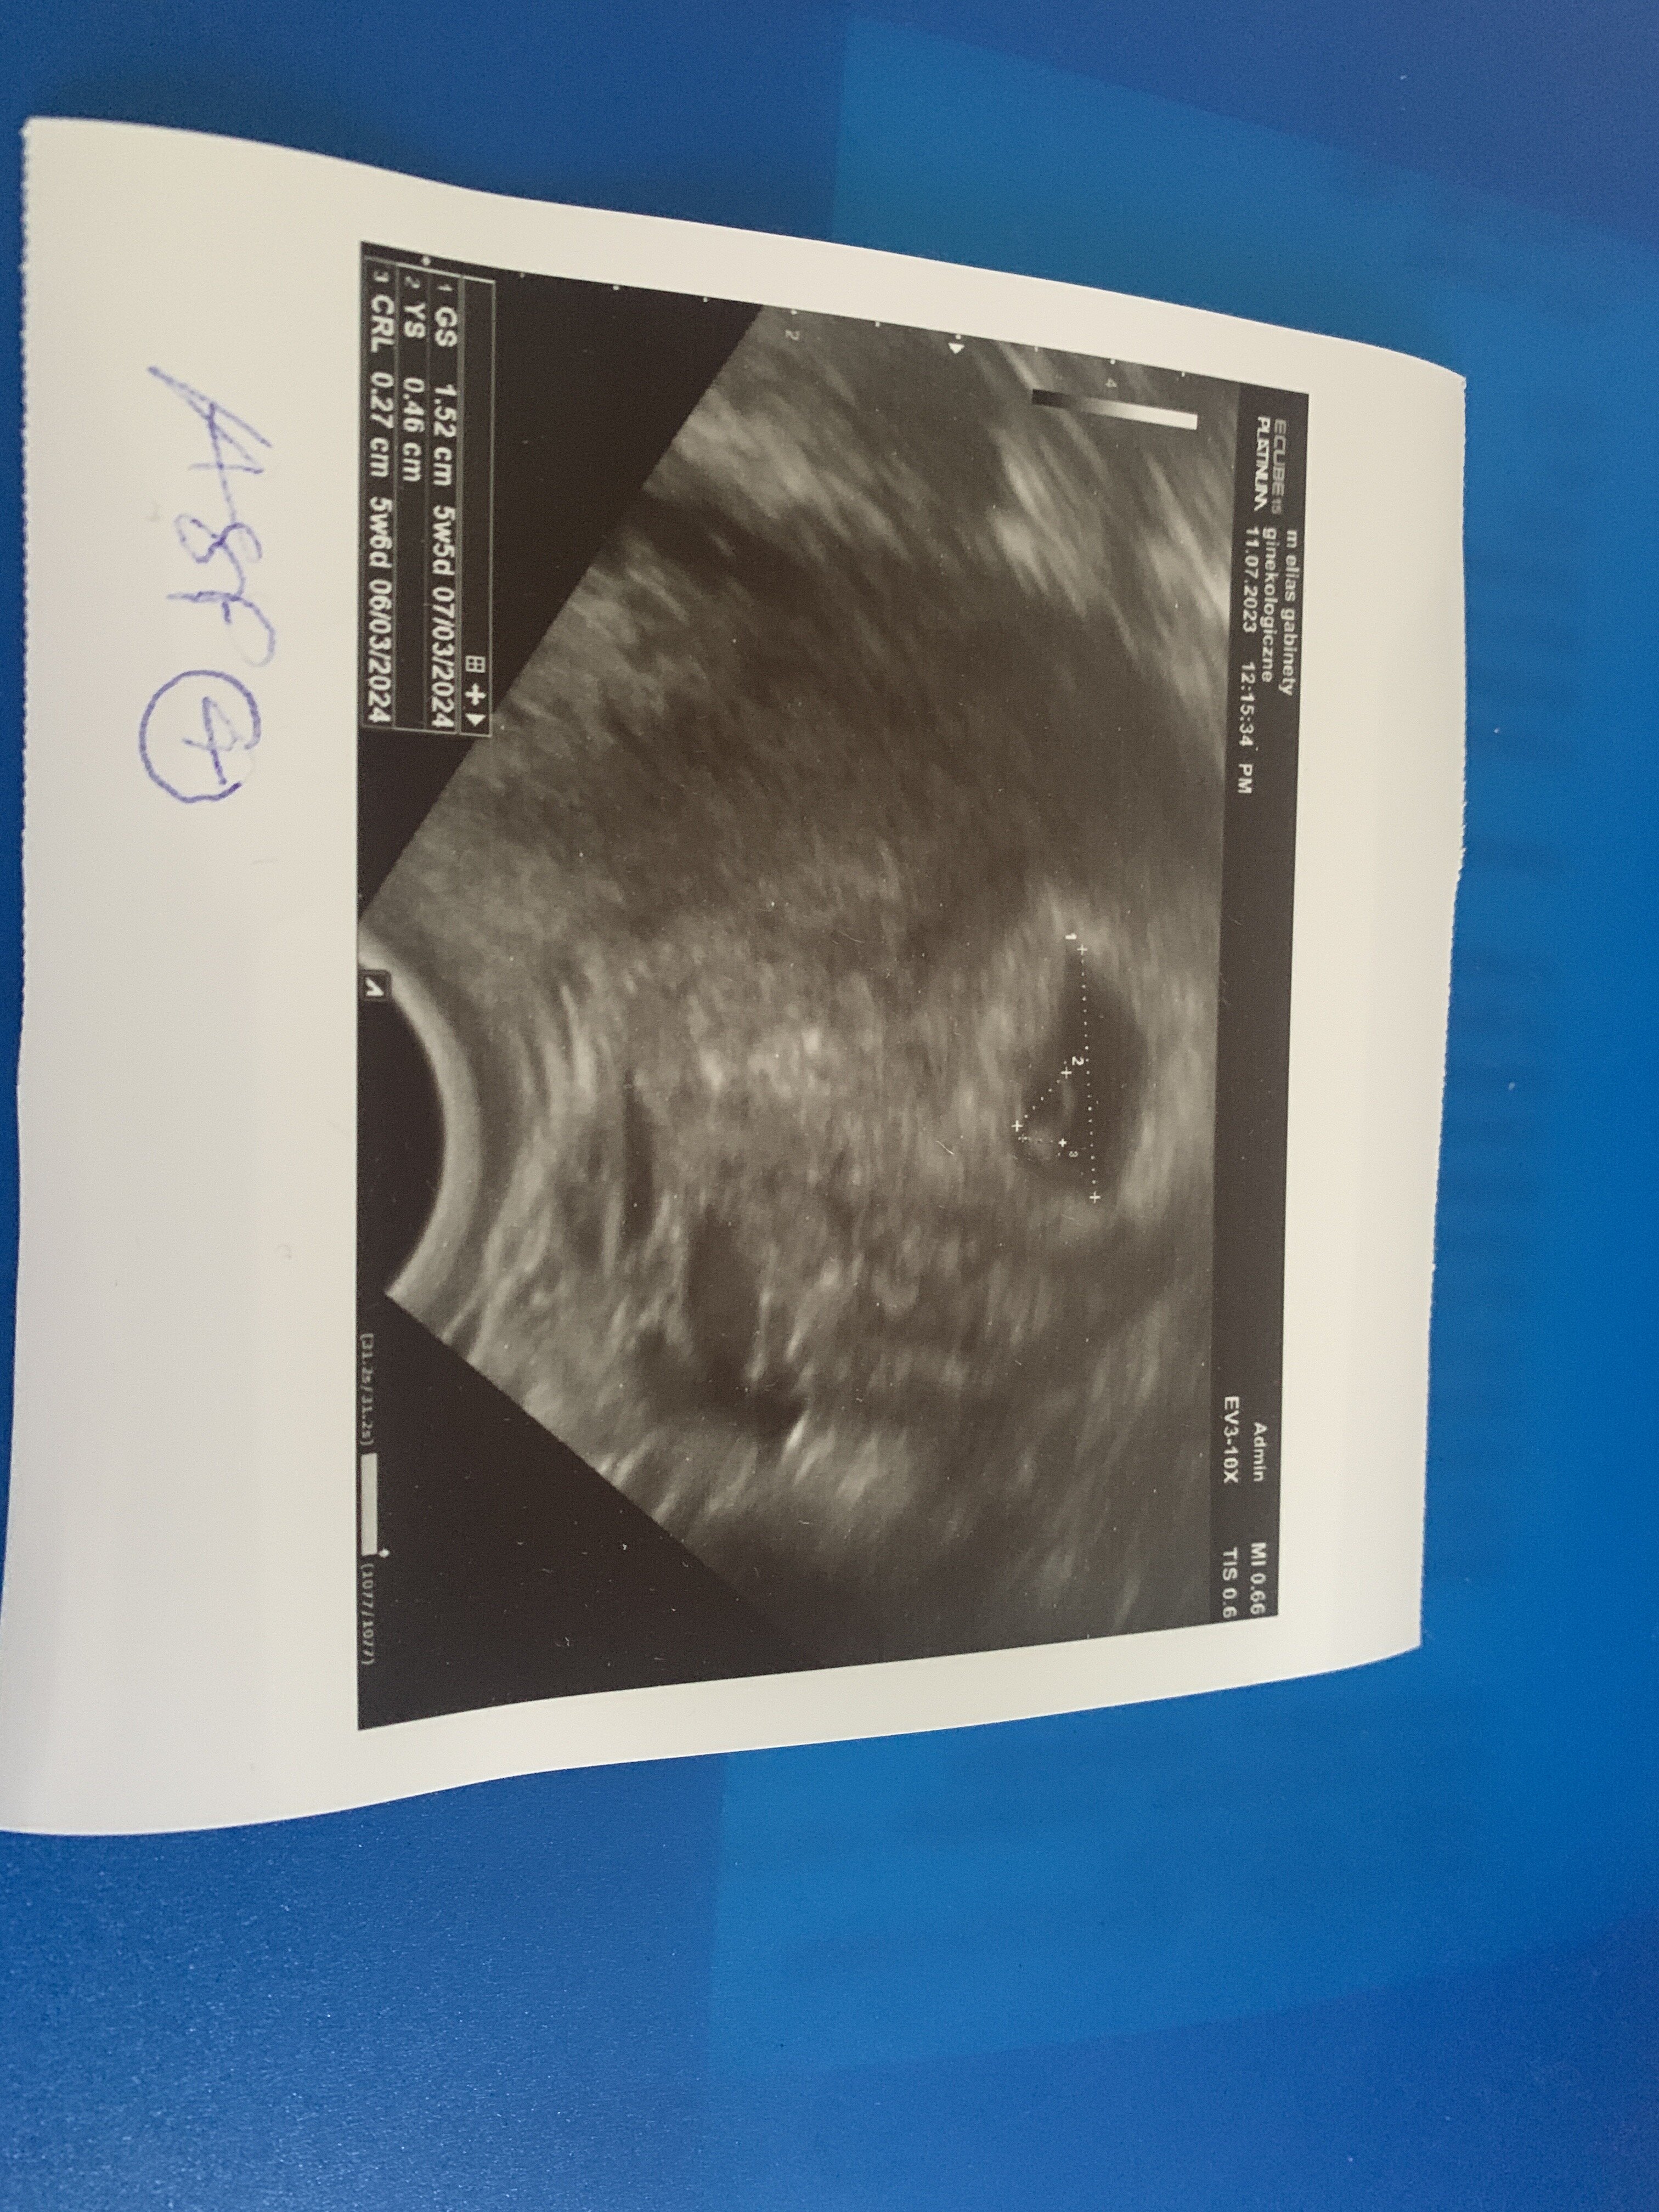

Ja już po wizycie ☺️

Wszystko dobrze słuchajcie, wyniki badań mam dobre ( przepisane mam kolejne ) a na USG było widać YS 💚 za tydzień już powinno być serduszko 🫣